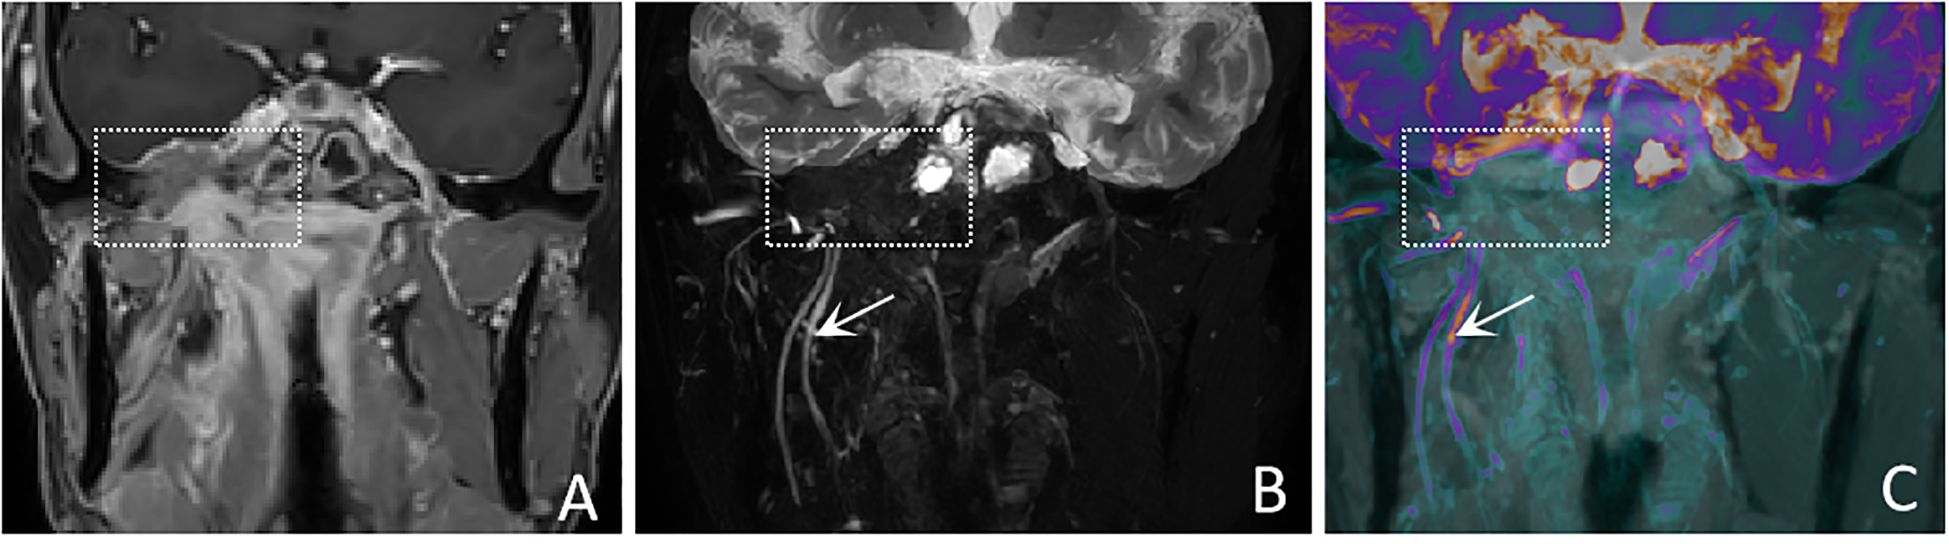

In terms of nerve involvement pattern, the neurogenic group predominantly exhibited focal involvement (92.9%), while the non-neurogenic group predominantly exhibited diffuse involvement (52.9%), with a statistically significant difference (p=0.002). Classical MRI findings showed a significantly higher incidence of the “dumbbell sign” in the neurogenic group compared to the non-neurogenic group (78.6% vs. 11.8%, p < 0.001). The “effacement of the fat plane” was exclusively observed in the non-neurogenic group, albeit with a relatively lower incidence (29.4%) (p < 0.001)(Table 3). Among the novel CE-MRN signs, the “enhanced target sign” (p=0.032) and “nerve tail sign” (p=0.018) were more common in the neurogenic group (Figure 2). Conversely, the incidence of the “nerve effacing sign” was more frequently observed in the non-neurogenic group (76.5% vs. 35.7%, p=0.033), which may indicate a malignant trend (Figure 3). No significant differences were noted between the neurogenic and non-neurogenic groups regarding enhancement patterns, nerve signal and morphology (Table 4).

Figure 3

MRI images presented in three panels: A, B, and C. Panels A and B show black and white coronal views of the head, with dotted rectangles highlighting specific areas. Panel B includes a white arrow pointing to vascular structures. Panel C features a colored overlay indicating different tissues, with a similar dotted rectangle and arrow.

Figure 3. A 50-years-old male with nasopharyngeal carcinoma involving the right trigeminal nerve presents with the “nerve effacing sign”. (A) A Coronal CE-T1WI scan demonstrates diffuse enhancement in the parapharyngeal space and muscles, with invasion into the right side of the middle cranial fossa. (white dashed boxes) However, the trigeminal nerve and its branches are not visualized. (B) A coronal CE-MRN image shows diffuse signal decrease in the region of the mandibular nerve., indicative of the “nerve effacing sign” (white dashed box). Additionally, the right inferior alveolar nerve and lingual nerve are thickened and exhibit significantly increased signal intensity (white arrows). (C) A coronal fused image simultaneously displays the lesion (white dashed box) as well as the involved trigeminal nerve and its branches (white arrows).

This study reveals that nerves are mainly affected focally in neurogenic tumors, whereas affected diffusely in the non-neurogenic malignancies. observation aligns with the localized expansive growth characteristics of benign neurogenic tumors such as schwannomas, and also reflects the pathological characteristics of malignant tumors spreading along the perineural spaces (1719). In the novel CE-MRN signs (14), the “Enhanced target sign” manifests as a central region of low signal intensity surrounded by a peripheral region of high signal intensity. The underlying formation mechanism may be related to the differential enhancement between the Antoni A zone (cell-dense zone) and the Antoni B zone (mucous-like matrix zone) in schwannomas (20). The “nerve tail sign” serves as a direct imaging marker for neurogenic tumors by directly demonstrates the anatomical continuity between the tumor and the host nerve (21). Additionally, the “nerve effacing sign” may serve as an indicator of malignant tumors with PNS. The solid components of the tumor, characterized by their abundant blood vascularity and contrast agent penetration, exhibit a diffuse signal reduction on CE-MRN. This imaging finding mimics the appearance of affected nerves being incorporated into the tumor mass (22). The novel series of signs offers a new perspective for assessing nerve involvement and tumor features.